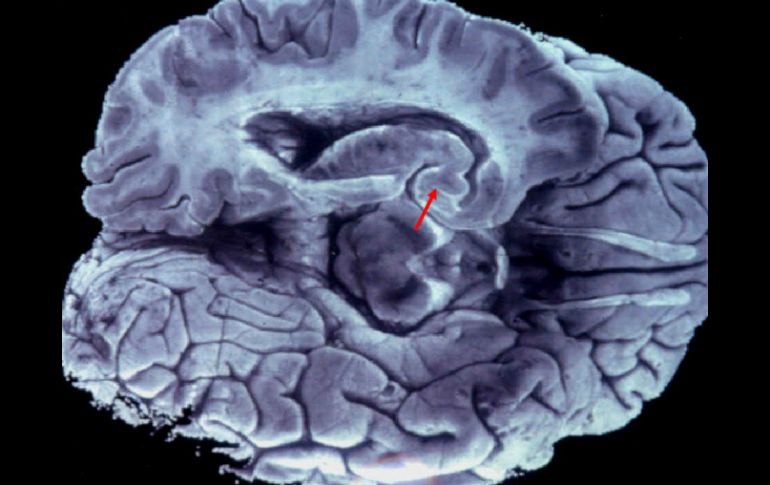

Tecnología | Analizaron en roedores neuronas del hipocampo Descubren mecanismo que puede ayudar a comprender males como el Alzheimer Se trata de un mecanismo clave para la formación, el robustecimiento y el funcionamiento de la sinapsis Por: EFE 13 de febrero de 2012 - 19:11 hs El estudio da una luz sobre cómo funciona la sinapsis. ARCHIVO / BUENOS AIRES, ARGENTINA (13/FEB/2012).- Científicos argentinos descubrieron un mecanismo que provee nuevos datos sobre el funcionamiento de la comunicación entre neuronas, lo que puede aportar vías para la comprensión de enfermedades como el mal de Alzheimer, informó hoy la investigadora a cargo del estudio. Se trata de un mecanismo clave para la formación, el robustecimiento y el funcionamiento de la sinapsis, es decir, el punto de comunicación entre las neuronas, precisó la Agencia de Ciencia y Técnica del Instituto Leloir, donde se desarrolló la investigación. El equipo identificó en este proceso de comunicación paquetes de la molécula llamada ARN mensajero temporalmente inactivos, a los cuales llamaron "focos de silenciamiento de mensajeros", explicó Graciela Boccaccio, jefa del Laboratorio de Biología Celular del Instituto Leloir. Cuando forman estos paquetes o agregados, los ARN mensajeros no pueden cumplir su misión, la cual permite consolidar la comunicación entre neuronas para la memoria y el aprendizaje. Los científicos también identificaron en este proceso la proteína Smaug 1, que cuando se bloquea, se produce un defecto sináptico muy serio y las neuronas se desarrollan de forma incompleta, según comprobaron durante el estudio. "Estos defectos son muy similares a lo que se observa en varias enfermedades neurodegenerativas", precisó Boccaccio. Para la investigadora, el estudio da una luz sobre cómo funciona la sinapsis y puede ayudar a crear nuevas vías para entender las enfermedades de este tipo, entre las que se encuentra el mal de Alzheimer y la esclerosis. Durante el trabajo, publicado en la revista The Journal of Cell Biology, los científicos analizaron en roedores neuronas del hipocampo, la región del cerebro asociada con los aspectos cognitivos. Temas Ciencia médica Enfermedades Alzheimer Lee También Julieta Fierro será homenajeada en la FIL INAPAM: ¿Cómo solicitar un turno para consulta médica gratuita? Nobel de Química premia el desarrollo de estructuras metal-orgánicas Nobel de Física para Clarke, Devoret y Martinis por descubrimiento sobre fenómenos cuánticos Recibe las últimas noticias en tu e-mail Todo lo que necesitas saber para comenzar tu día Registrarse implica aceptar los Términos y Condiciones